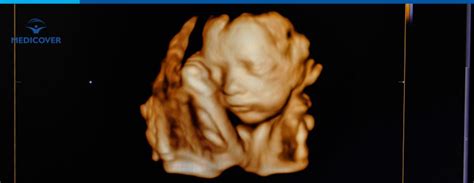

Examinarea Ecografică (Ecografia de Morfologie Fetală de Trimestrul I)

Ecografia permite vizualizarea unor caracteristici ale fătului, cunoscute sub denumirea de "soft markers", care pot sugera prezența unor probleme cromozomiale. Un parametru crucial măsurat este lungimea cranio-caudală (CRL), utilizată pentru a confirma vârsta gestațională corectă pentru efectuarea testului. De asemenea, se măsoară nivelul de lichid acumulat la nivelul cefei copilului, cunoscut sub denumirea de translucență nucală (NT). Un os nazal vizibil sau absent poate oferi, de asemenea, informații suplimentare.

Interpretarea corectă a rezultatelor dublului test se face întotdeauna în contextul unei ecografii de translucență nucală și a vârstei viitoarei mame. Un lichid acumulat în exces în zona cefei fătului, vizibil la ecografie, poate indica un risc crescut de anomalii cromozomiale și poate justifica investigații suplimentare, precum cariotipul din lichid amniotic sau din vilozități coriale.